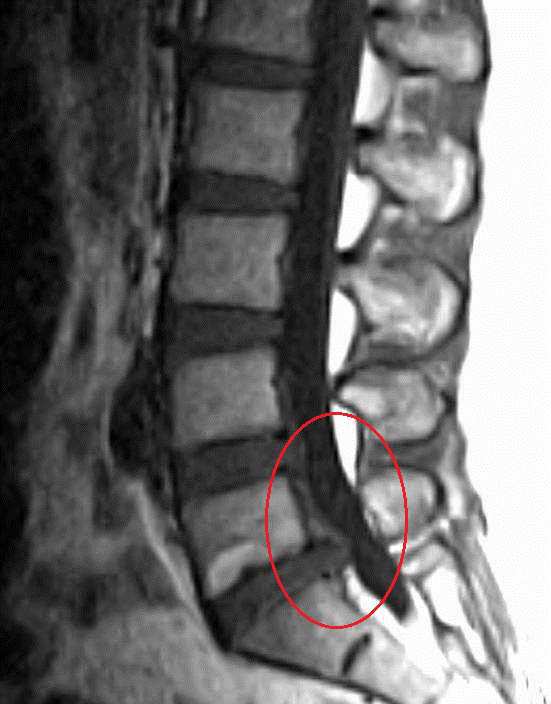

- 디스크파열은 섬유륜 후위부에서 잘 일어나고 신경종말이 있는 부위로 뻗어간다. 단순 파열은25세경 첫 증상을 느끼는 경우가 많다.

- 신경내 모든 구조물이 동통 진행과 관계되는데 디스크는 어린 나이에 시작되고 디스크를 제외한 모든 구조물의 변화는 주로 노년에 나타나며 심한 퇴행성 디스크 증세를 가져온다.

- 디스크의 퇴행은 방사선 검사시 50-60대 사람에게서 흔하며 요통이 있는 사람들이 없는 사람보다 더 많이 퇴행되어 있다.